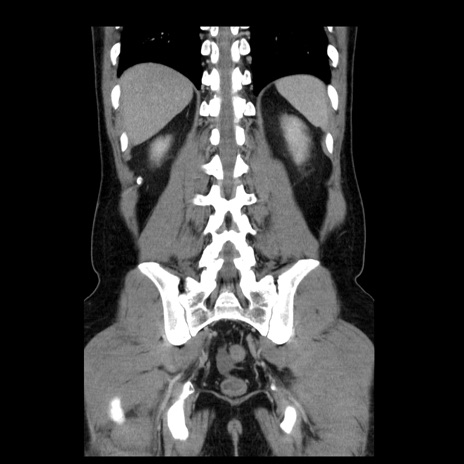

横断像

【症例】30歳代男性

【主訴】腹痛、嘔吐

【現病歴】昨晩から突然の腹痛あり、その後嘔吐、軟便も出現。腹痛が改善しないため救急搬送となる。2日前にしめ鯖の食事歴あり。

【身体所見】意識清明、苦悶様、BP 135/90mmHg、BT 35.7℃、腹部:平坦、やや硬、心窩部〜臍部に自発痛、圧痛あり、筋性防御+、反跳痛-

【データ】WBC 8100、CRP 0.57